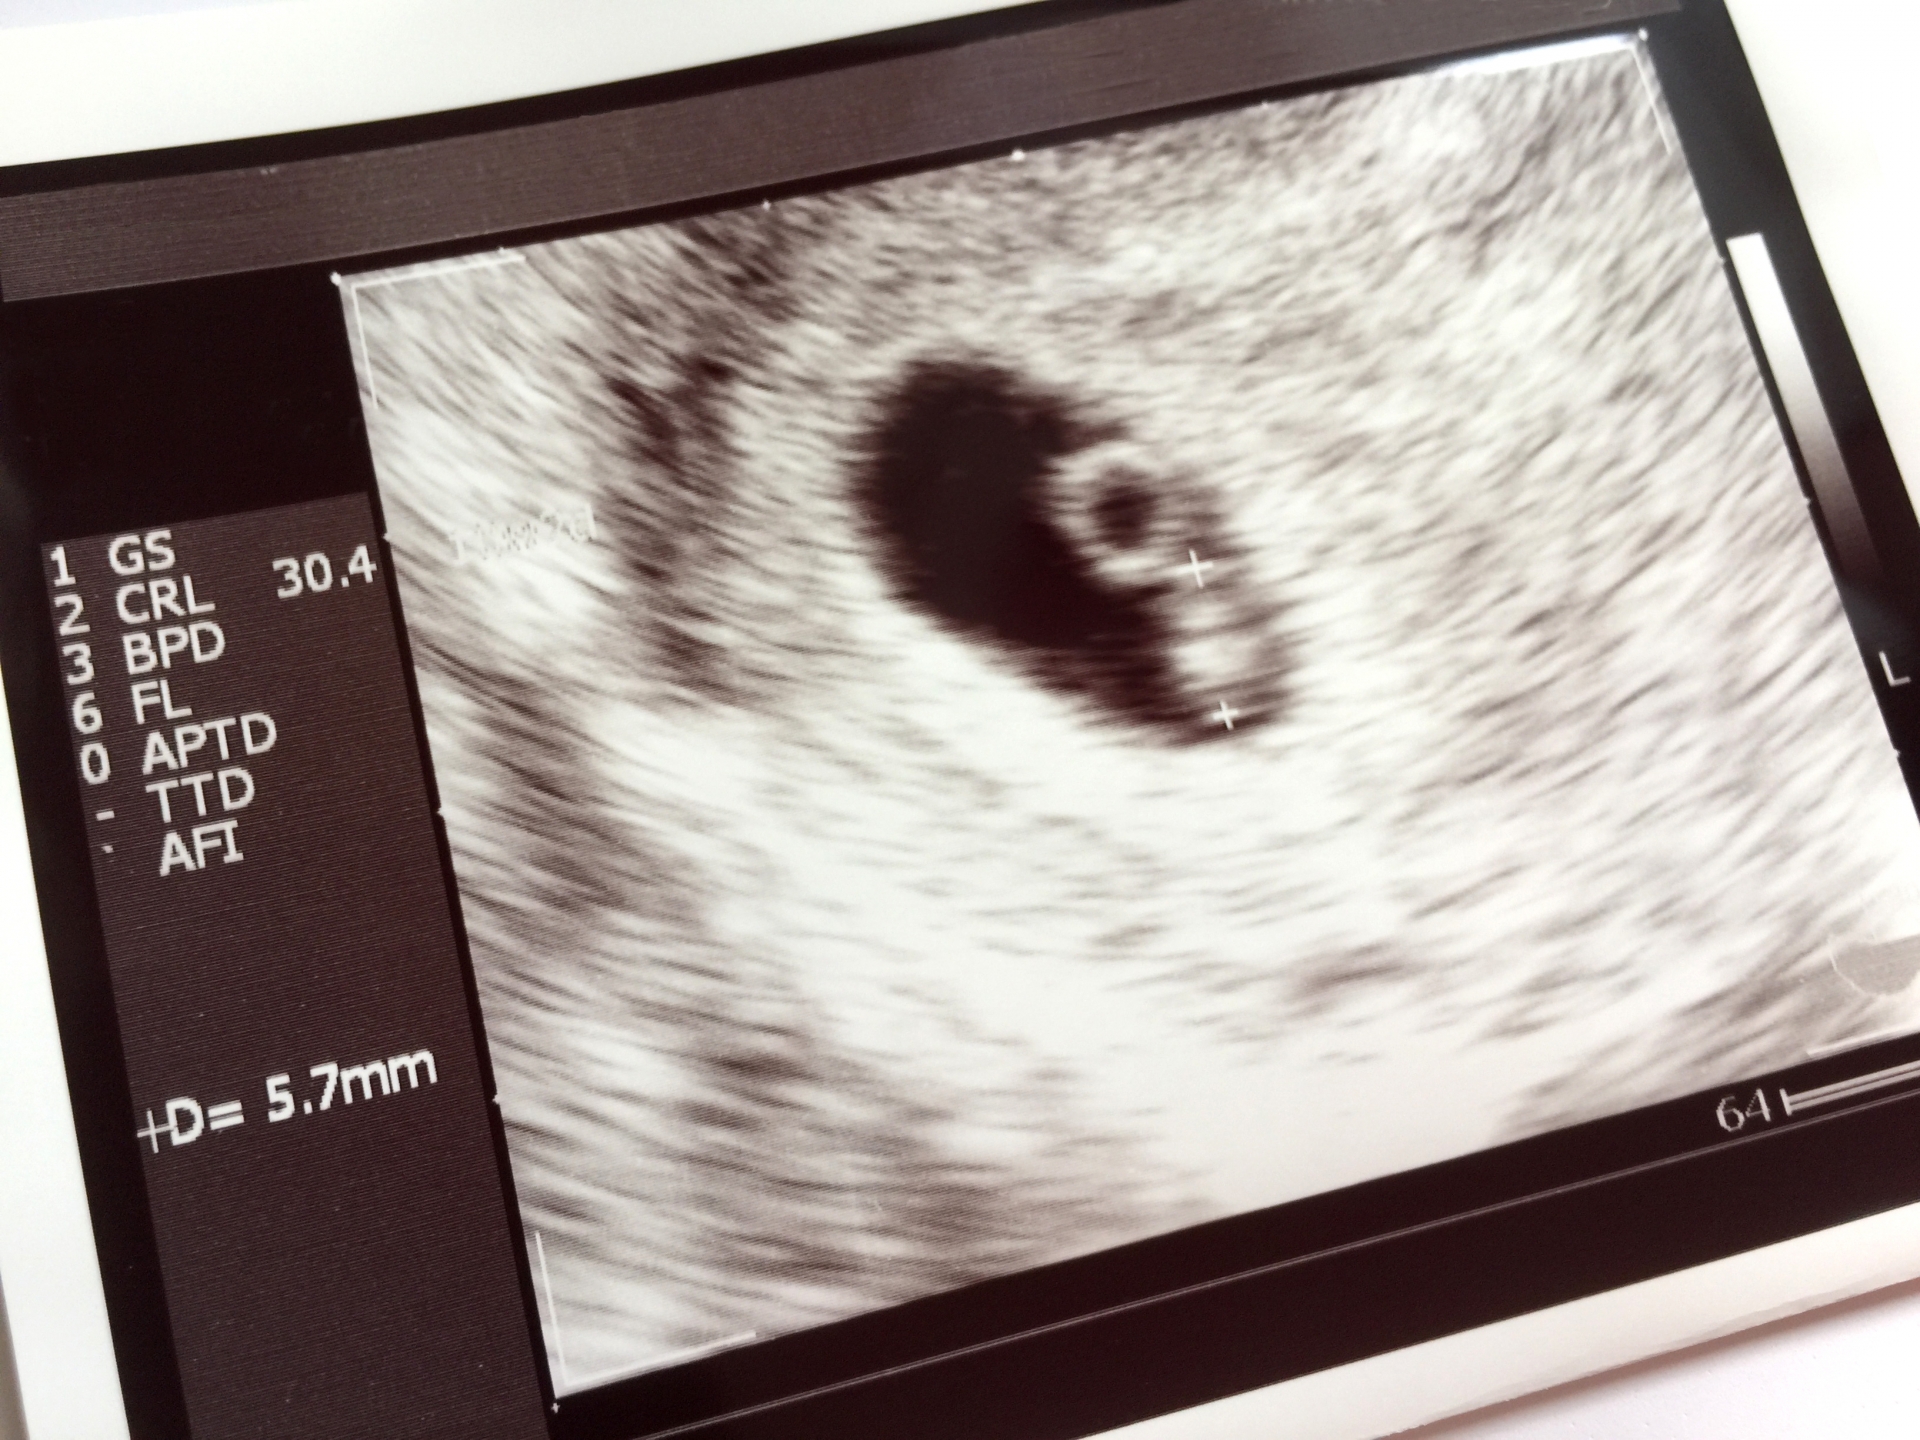

しかし、多くのママが「妊娠したかも?」と気づいて検査薬を使うのは、早くても妊娠4週〜5週頃。産婦人科に来る頃には、赤ちゃんの神経の基礎はすでに完成間近(または完成した後)なのです。